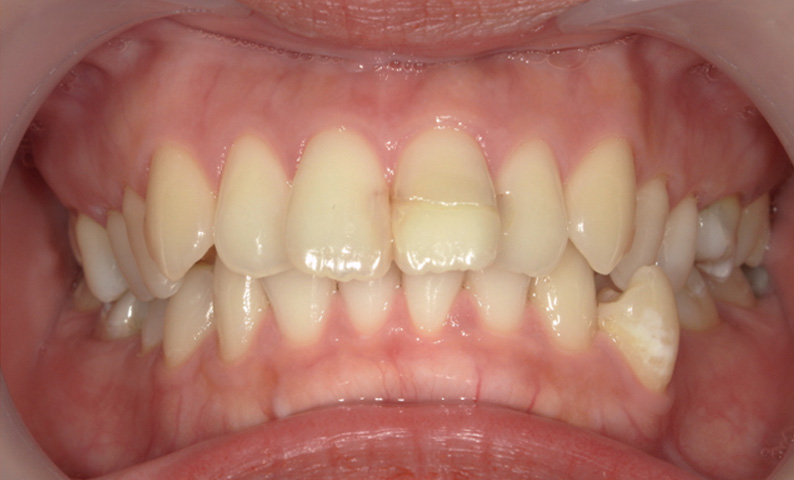

症例_012 「出っ歯」症例

治療期間:8ヶ月金額:30万円+税20代女性出っ歯上の前歯だけ

| Before | After |